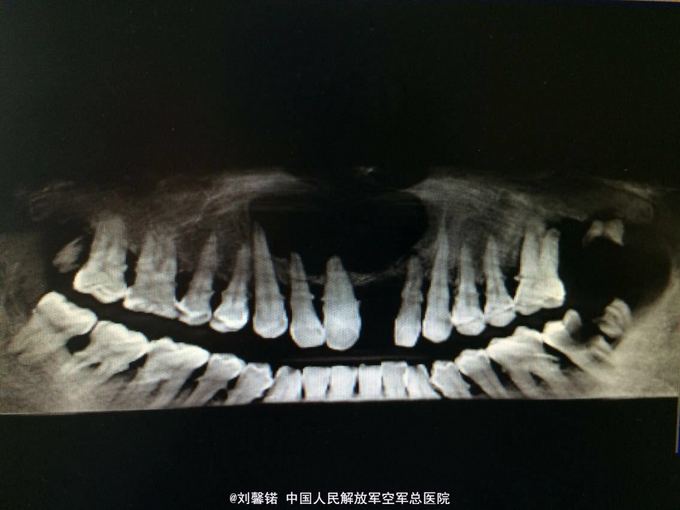

检查:右上唇鼻下区肿胀,口腔卫生差,牙石(+).21缺失,22-13前庭沟变浅,黏膜肿胀,牙不松动,无疼痛,舌.腭均侧有不同程度的膨隆,扪诊囊性感,牙髓活力,13~23分别为32.64.64.64.44辅助检查:cbct示:13~22根尖区卵圆形密度减低区,边界清楚,边缘光滑锐利,周围骨质吸收,囊腔壁为致密白线。囊肿上界与鼻底仅余薄层骨质.穿刺检查:穿刺液为草黄色液体